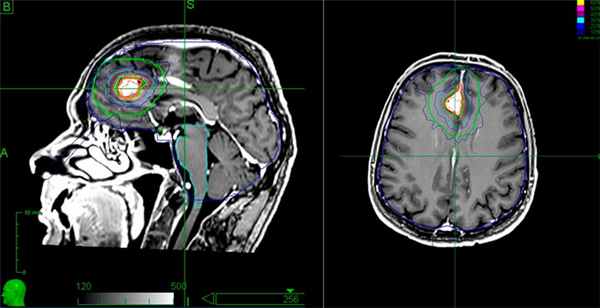

Лечение менингиомы. Этапы подготовки мишени для облучения на системе "Кибер-нож”

Кибер-Нож позволяет удалить опухоль без боли и повреждения важных структур мозга. Процедура проводится в амбулаторных условиях без госпитализации пациента, после терапии пациент сразу может ехать домой. В ПЭТ-центре план лечения составляется врачами радиологом и онкологом, что позволяет выбрать наиболее эффективную тактику для конкретного пациента.